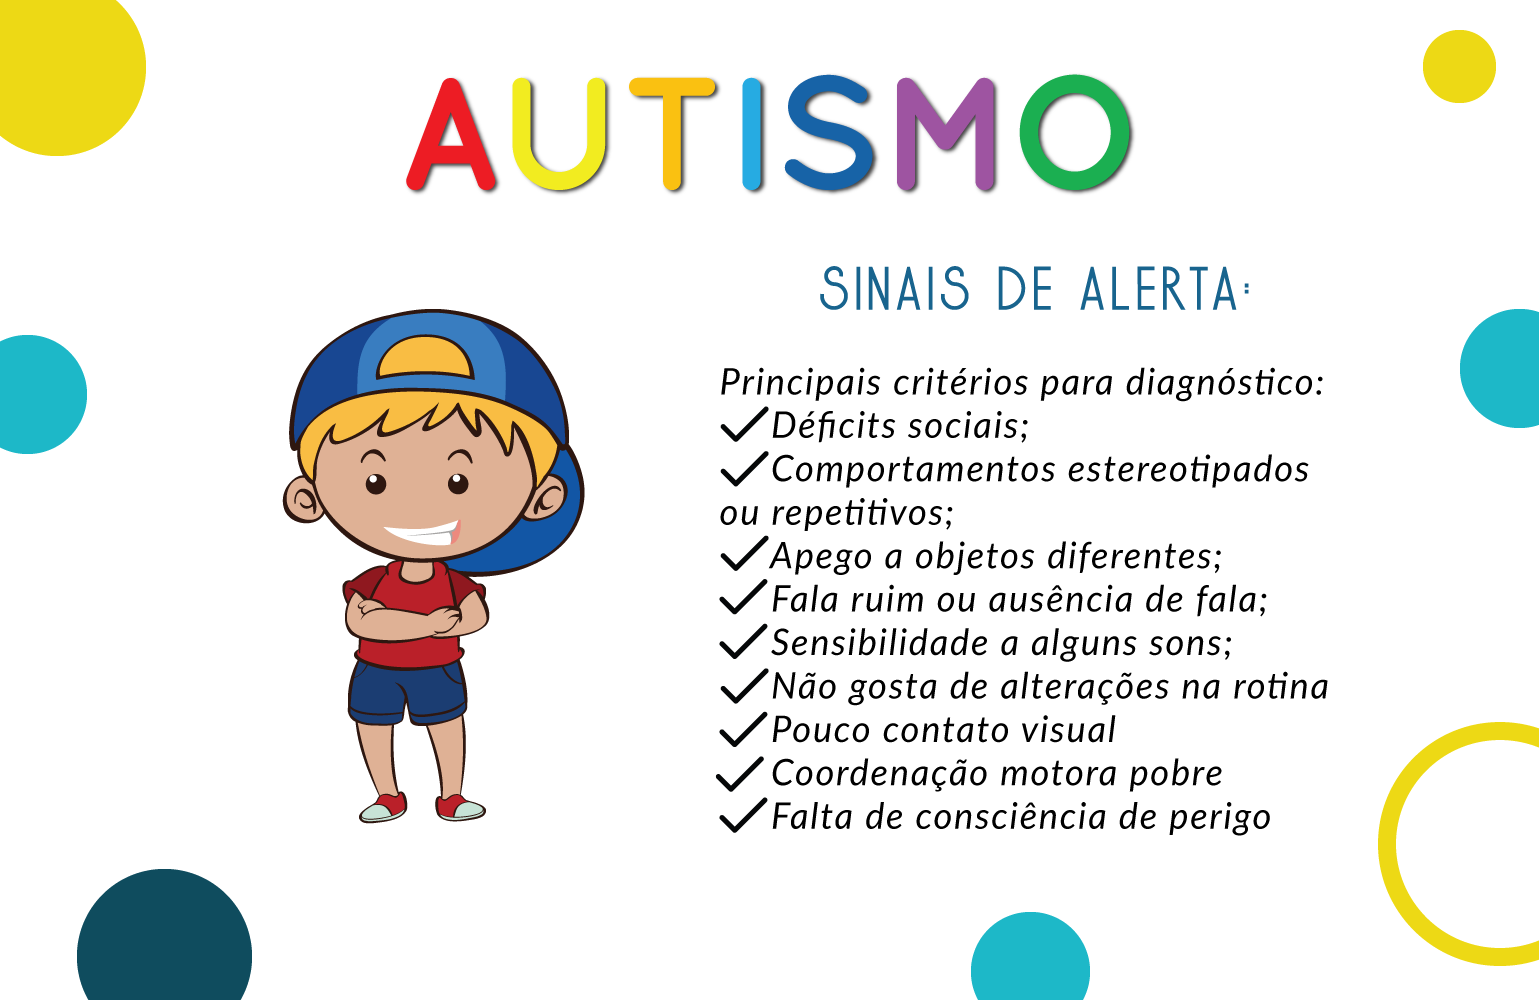

Conheça os Sinais do Autismo

Conheça os primeiros sinais do Autismo! - Blog Rhema Educação04 abril 2025

Conheça os primeiros sinais do Autismo! - Blog Rhema Educação04 abril 2025 -

TOK & ART'S DA PROFESSORA LI: SINAIS DE AUTISMO.04 abril 2025

TOK & ART'S DA PROFESSORA LI: SINAIS DE AUTISMO.04 abril 2025 -